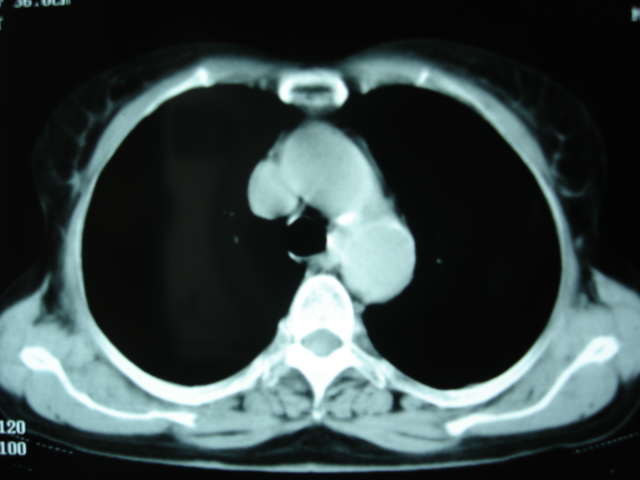

以下是引用卜一在2009-9-7 19:51:00的发言:[br][br] 1 左侧胸内甲状腺占位-多考虑甲状腺腺瘤! 2、左肺门占位-建议增强扫描以便明确性质。 3 慢支并感染! [br]

以下是引用shibing在2009-9-7 20:40:00的发言:[br]左侧胸内甲状腺占位-多考虑甲状腺腺瘤! 2、左肺门占位-建议增强扫描以便明确性质。 3 慢支并感染! [br]